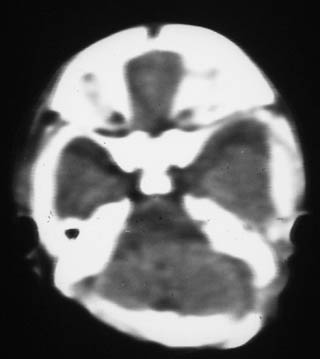

透明隔缺如

透明隔缺如。

这是一个早产儿(大约34周左右)的片子,可以是透明隔缺如,但往往是错误的。

是不是只听过没见过的视隔发育不良?

是个早产儿,不过没那末早,提前了26天。

没有准确结果,病人家属拒绝做mr,3天后新生儿情况稍有稳定后,就出院了。

视-隔发育不良:视-隔发育不良是罕见的中线结构前部畸形,主要特征为透明隔缺如,一般常见于垂体性侏儒症。ct表现为正常的透明隔缺如,双侧侧脑室前角及体部融合为一单脑室,侧脑室及第三脑室中度扩大,侧脑室前角在轴位像上呈反三角形,胼胝体压部变薄。约半数患者还伴有其它脑裂畸形改变。

胼胝体发育不全:胼胝体发育不全病因未完全确定,与遗传因素、母体感染或血管因素有关。胼胝体发育不全还可合并半球间裂囊肿、脂肪瘤、透明隔发育不全等。ct表现:半球间裂过深,第三脑室向前上移位,两侧侧脑室扩大,体部分离,呈反“八”字型或平行状。可伴随脑裂畸形、巨脑回、半脑间裂、蛛网膜囊肿及透明隔缺如等

透明隔缺如,支持。